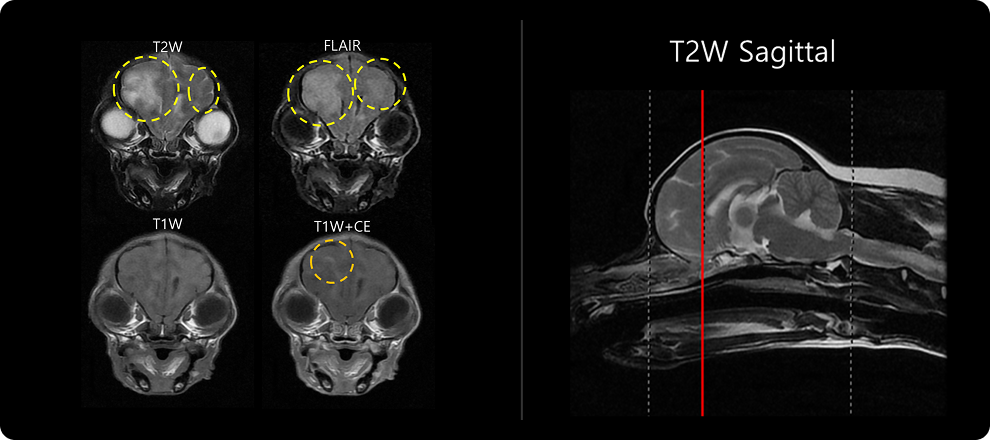

· MRI 검사

MRI 검사는 다양한 촬영 기법을 이용해 뇌질환을 감별하는 검사입니다. 뇌수막염에서는 뇌 부종성 병변, 괴사 병변, 뇌수막 변성 및 조영 증강, BBB(뇌혈관장벽) 손상 여부를 중점적으로 확인합니다. 이 단계에서 뇌와 척수의 구조적 이상, 염증의 위치와 범위를 파악합니다. 앞서 진행한 병력 청취 및 신경계 검사를 바탕으로 촬영 부위를 설정하며, 부위는 두개, 경추, 흉요추, 요천추 등으로 나뉩니다.

1-1 1-2 1-2 1-2

비감염성 뇌수막염은 아래와 같은 조직검사상의 분류로 분류되나, MRI 검사 상에서 분류는 한계가 있으며 MRI 상의 병변을 통해 질병 계통을 추정하게 됩니다.

• GME (Granulomatous Meningoencephalitis) 과립세포성 염증

• NME (Necrotizing Meningoencephalitis) 괴사성, 뇌회백질 위주 병변

• NLE (Necrotizing Leukoencephalitis) 백질 우세, 비대칭 병변